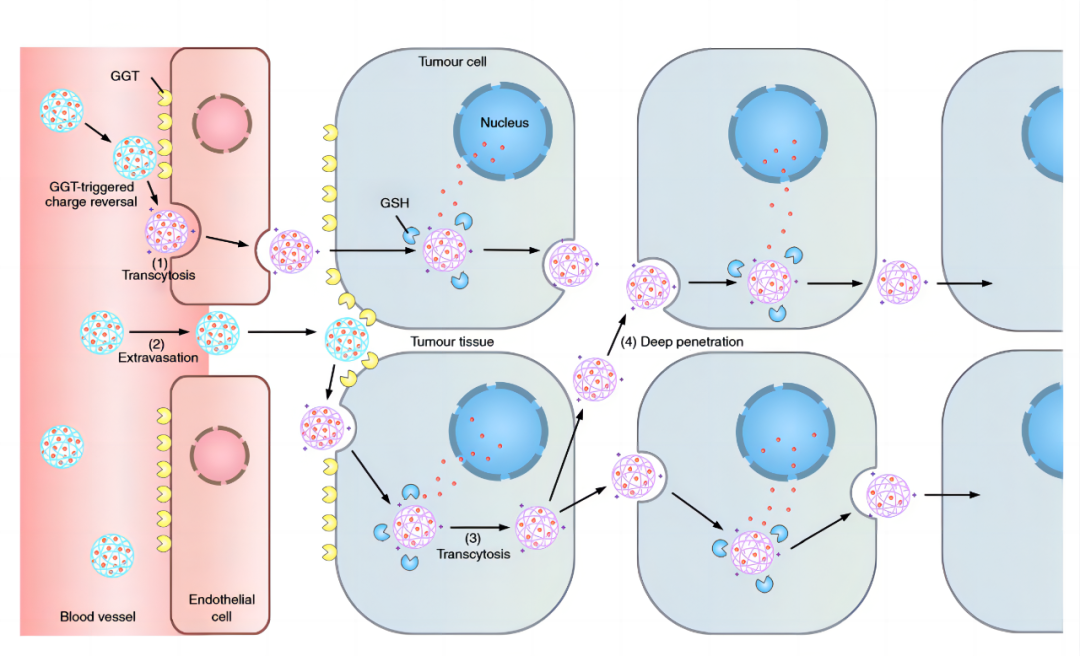

创新药胰腺癌纳米创新药PLAT001

普利制药与浙江大学联合创制的胰腺癌纳米创新药PLAT001,已经获得美国FDA临床试验批件。这是我国自主研发的首个在美国获批临床试验的纳米药物,体现了我国医学研究领域里程碑式的进步。标志着海南普利进入到生物医药、纳米科技、新材料等新领域。近期,PLAT001核心专利荣获海南省专利优秀奖。